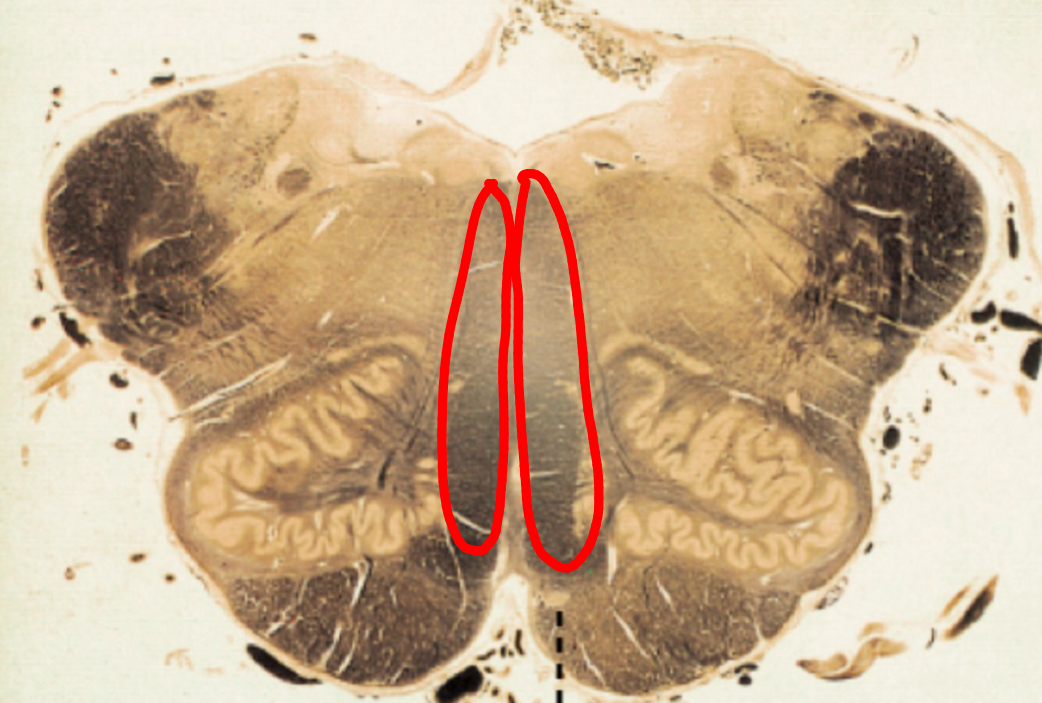

fastigial nucleus

interposed nucleus (globose + emboliform)

dentate nucleus

posterior lobe

vermis